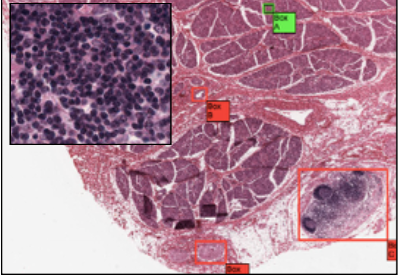

Where has this been taken from?

The tongue.

Contains mixed sero-mucous salivary glands

Lymph nodes - particullary in the posterior 1/3rd of tounge (linguninal tonsils)

Coarse multi-directional skeletal muscle bundles